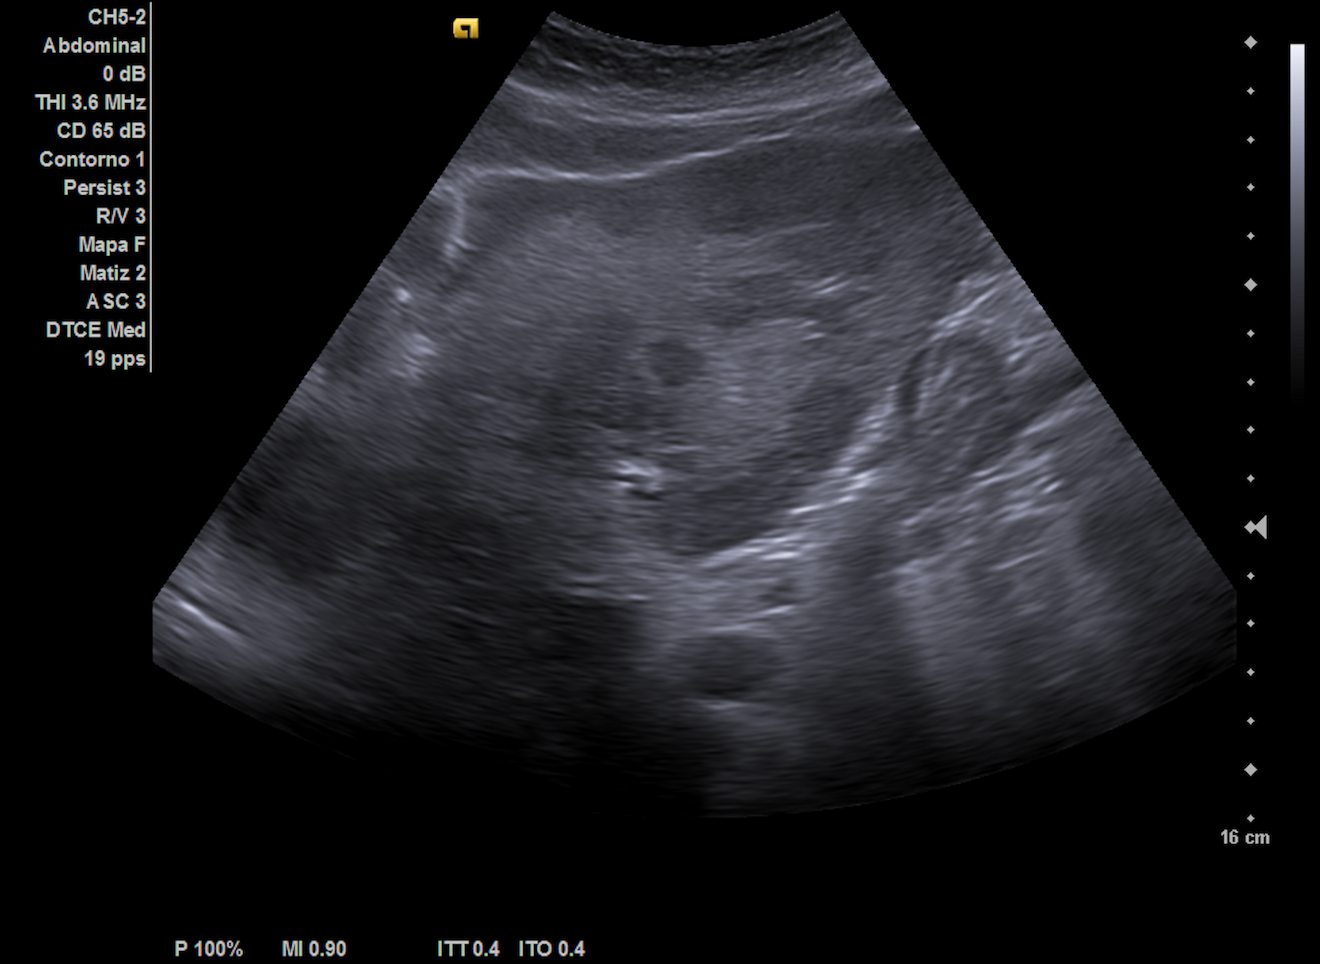

Ecografía hepática: hígado de tamaño normal con ecoestructura heterogénea, lesiones focales con halo hipoecoico en ambos lóbulos, sugerentes de metástasis. Las imágenes ecográficas del ingreso coincidían con nuestra descripción.